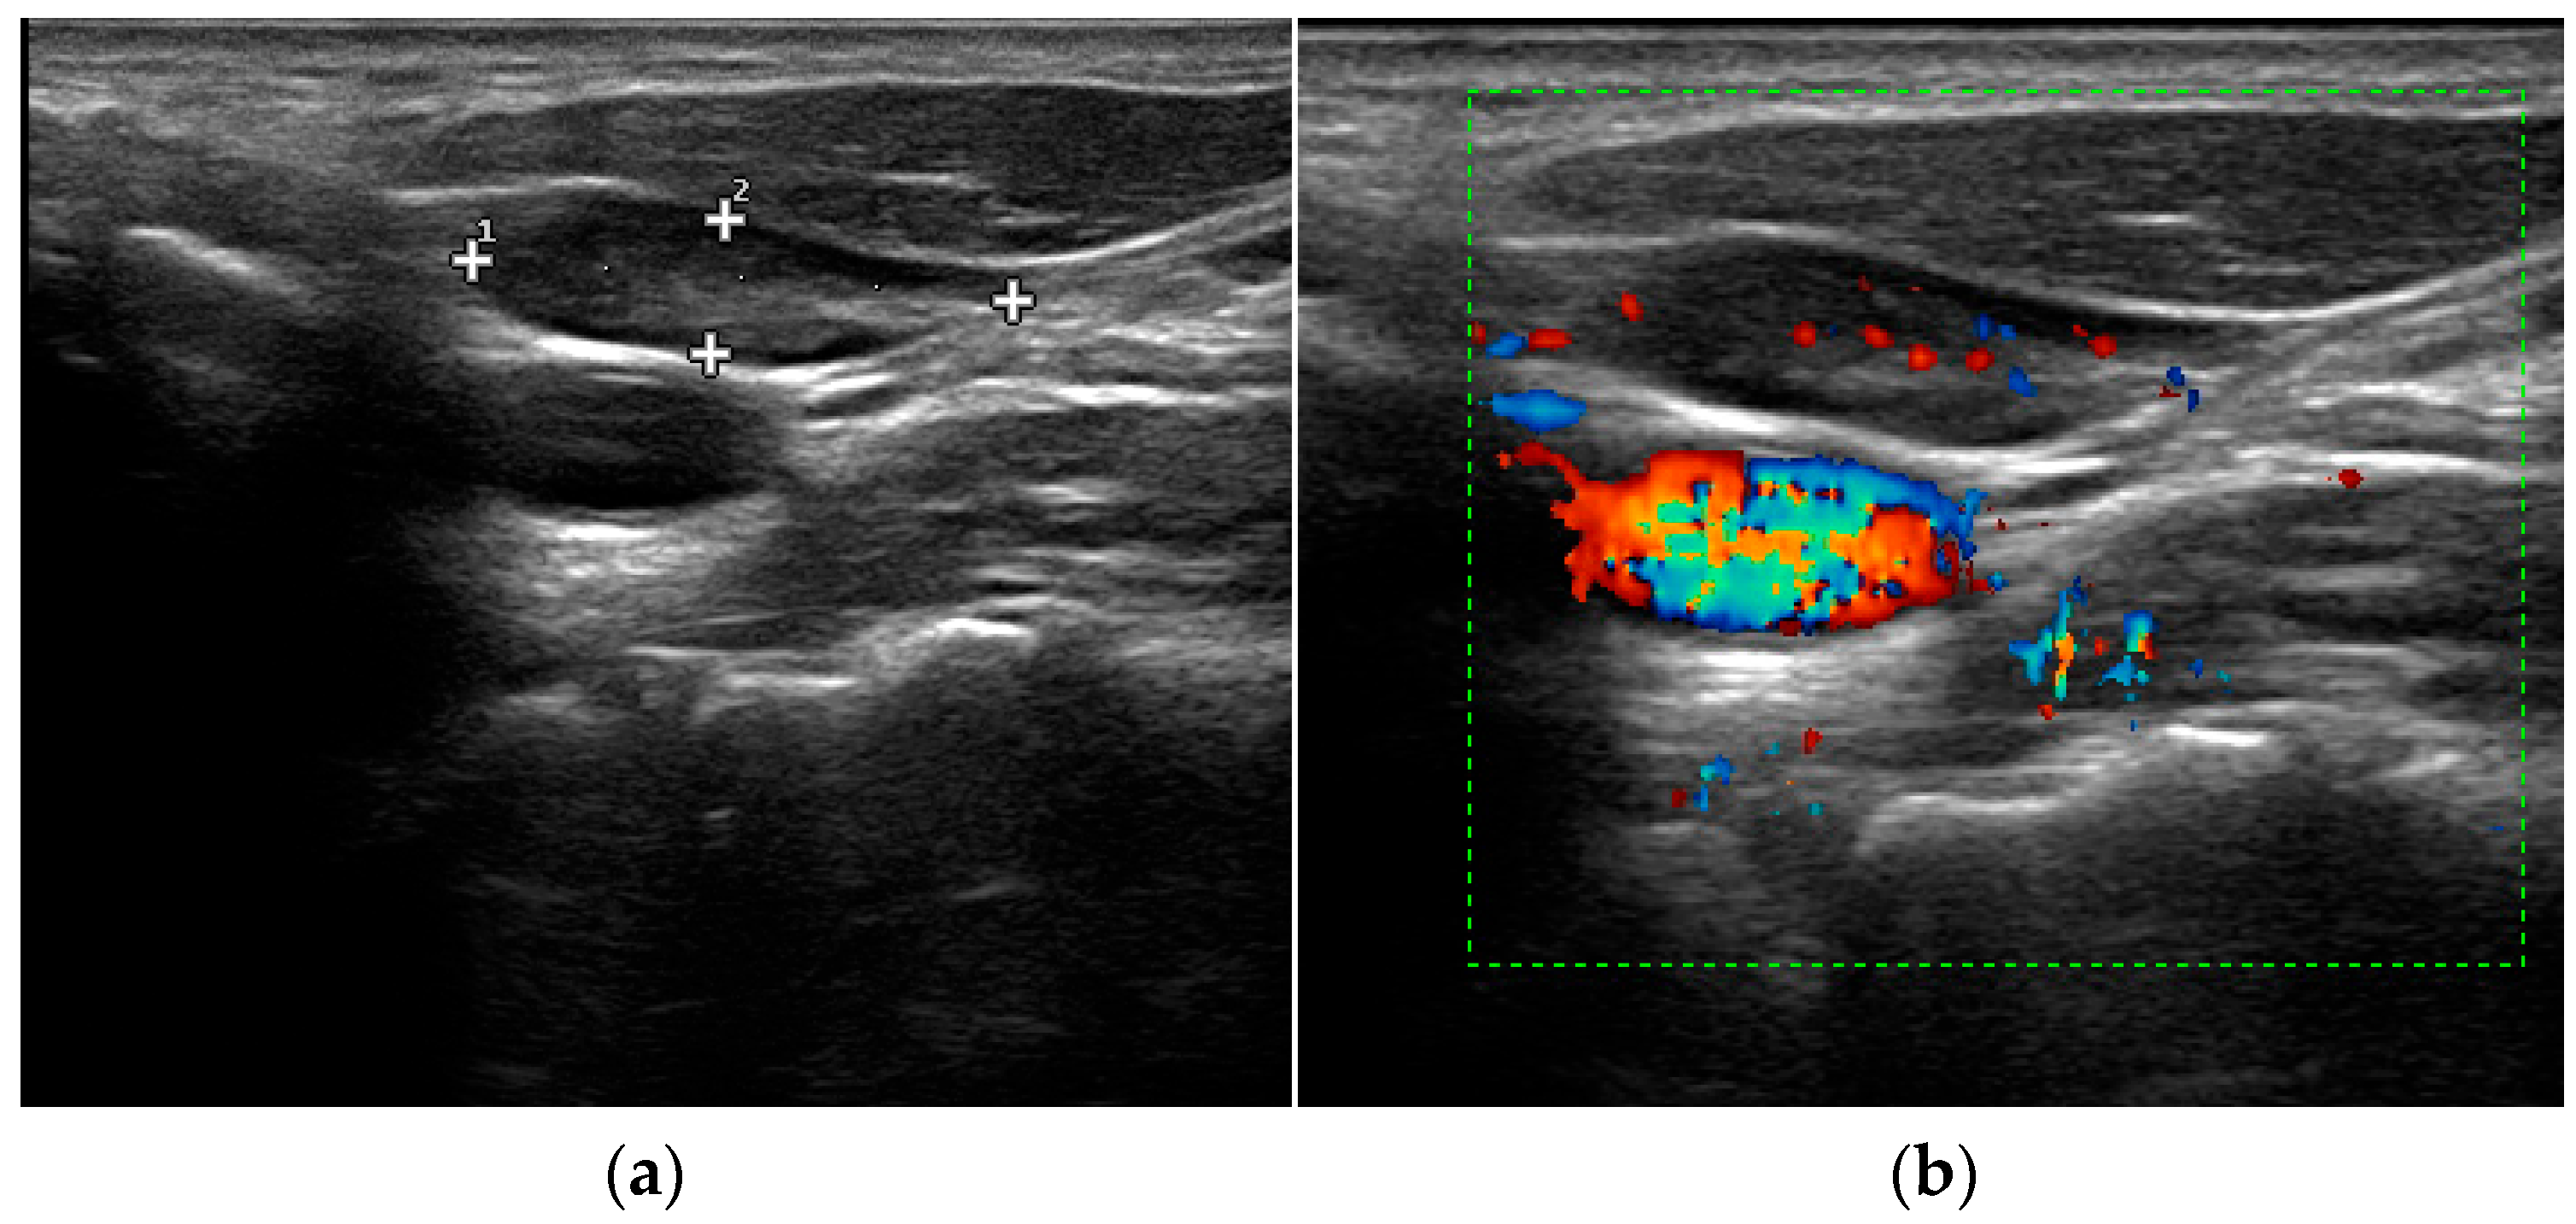

- Mohammadi, A.; Moloudi, F.; Ghasemi-rad, M. The role of colour Doppler ultrasonography in the preoperative localization of parathyroid adenomas. Endocr. J. 2012, 59, 375–382. [Google Scholar] [CrossRef]

- Vitetta, G.M.; Ravera, A.; Mensa, G.; Fuso, L.; Neri, P.; Carriero, A.; Cirillo, S. Actual role of color-doppler high-resolution neck ultrasonography in primary hyperparathyroidism: A clinical review and an observational study with a comparison of (99m)Tc-sestamibi parathyroid scintigraphy. J. Ultrasound. 2019, 22, 291–308. [Google Scholar] [CrossRef]

- Liu, H.; Liao, Q.; Wang, Y.; Hu, Y.; Zhu, Q.; Wang, L.; Liu, Q.; Li, J.; Jiang, Y. A new tool for diagnosing parathyroid lesions: Angio plus ultrasound imaging. J. Thorac. Dis. 2019, 11, 4829–4834. [Google Scholar] [CrossRef]

| Parathyroid hyperplasia | More than one symmetrically or asymmetrically enlarged, hypoechoic, oval shaped, lobulated gland. Significantly smaller than adenoma. Cystic inclusions may be seen. | Feeding polar vessels entering the pole and then extending around the periphery. | Fast intense homogeneous enhancement. Fast homogeneous wash-out. | Stiffer than proper parathyroid glands. |

| Parathyroid adenoma | Enlarged, circumscribed, hypoechoic, oval shaped lesion, delineated by hyperechoic halo. Cystic inclusions may be seen. | Feeding polar vessels entering the pole and then extending around the periphery. | Early peripheral hyperenhancement. Central wash-out in the later phases. | Stiffer than hyperplastic parathyroid glands. |